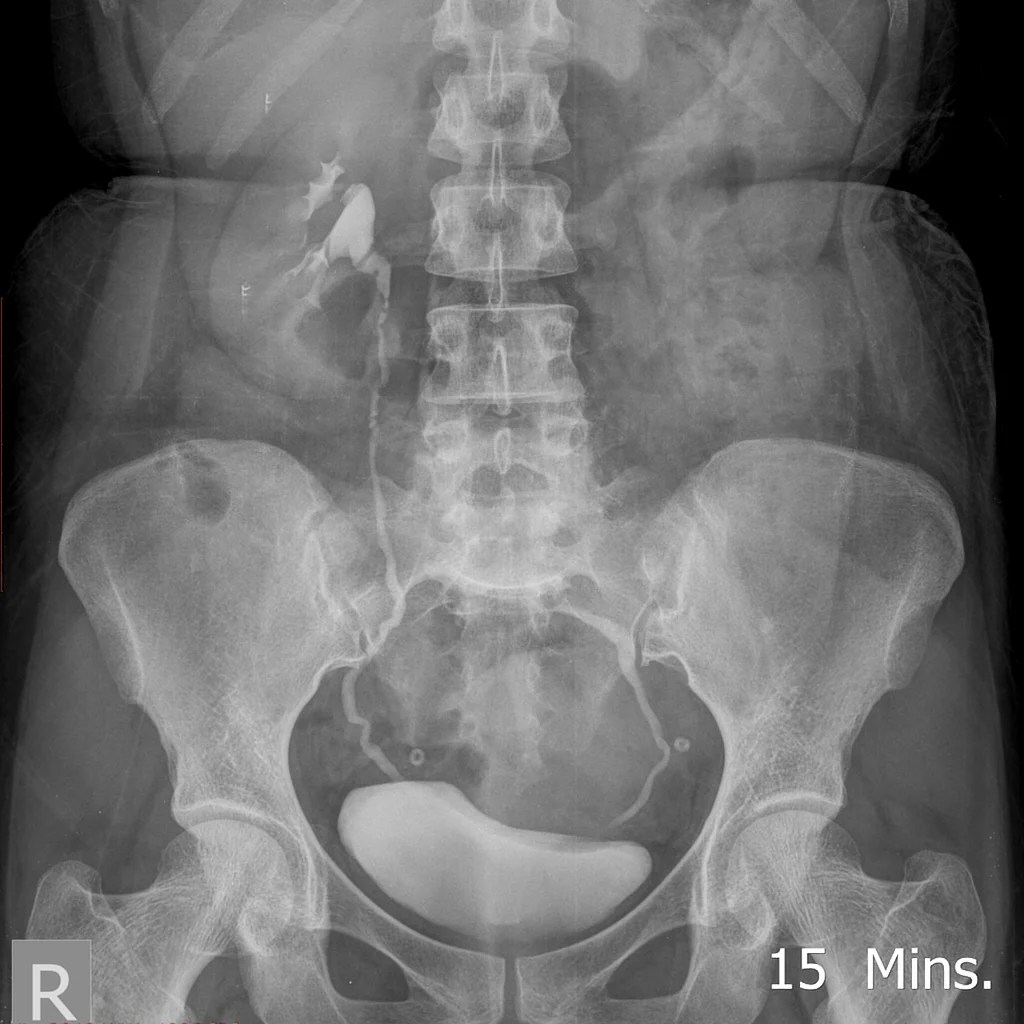

The medical name for hanging or prolapsed kidney is nephroptosis or renal ptosis. Condition of stones in the kidney a. Protrusion of the bladder a. In some individuals, symptoms occur when standing and are often relieved when lying down.

In some cases, nephroptosis can cause severe symptoms, including flank pain and blood in. Most people with nephroptosis have no symptoms at all. Narrowing of the ureter a. In some cases, nephroptosis can cause severe symptoms, including flank pain and blood in.

In some cases, nephroptosis can cause severe symptoms, including flank pain and blood in. Protrusion of the bladder a. Condition of stones in the kidney a. In some individuals, symptoms occur when standing and are often relieved when lying down.